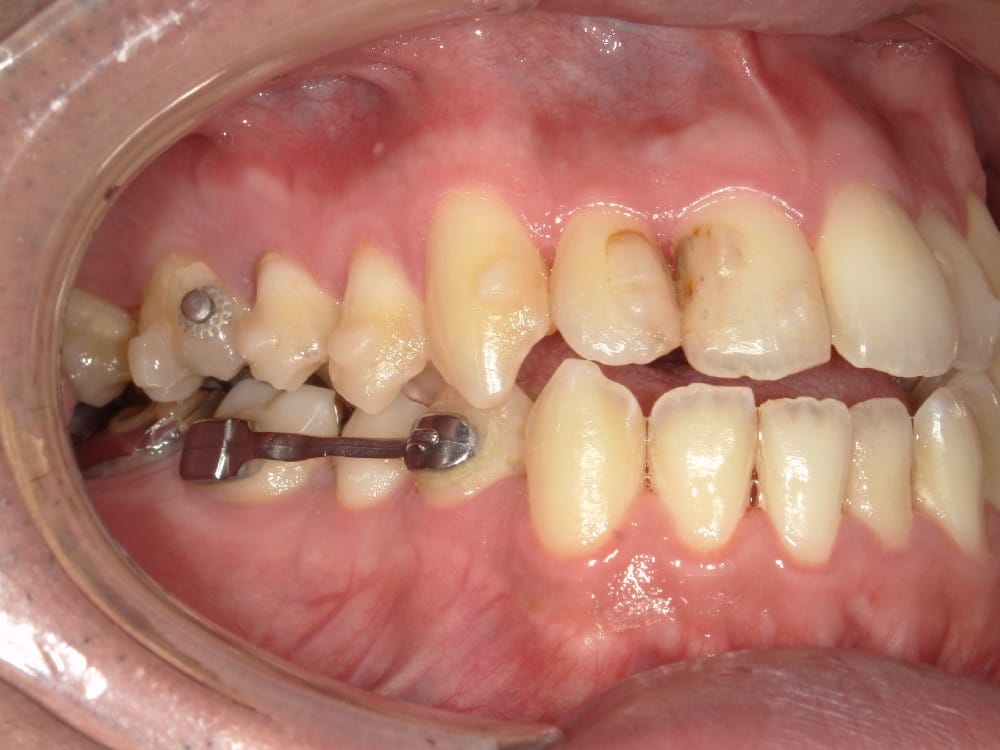

最後の画像のように奥歯のズレが1本以上あるケースでは、歯列矯正のみでの受け口の改善は困難と判断することが多いです。

このような奥歯の移動量が大きい症例では、マウスピースだけでは難しいことがあり、カリエールとよばれる装置を補助的に使用し、上下の噛み合わせの前後関係を整えることで、手術を行わずに機能面と見た目の両方が改善することがあります。

今回のケースも奥歯の移動量が大きいため、マウスピースだけでは難しいと判断し、カリエールとよばれる装置を補助的に使用し、上下の噛み合わせの前後関係を整えることで、手術を行わずに機能面と見た目の両方が改善することにしました。